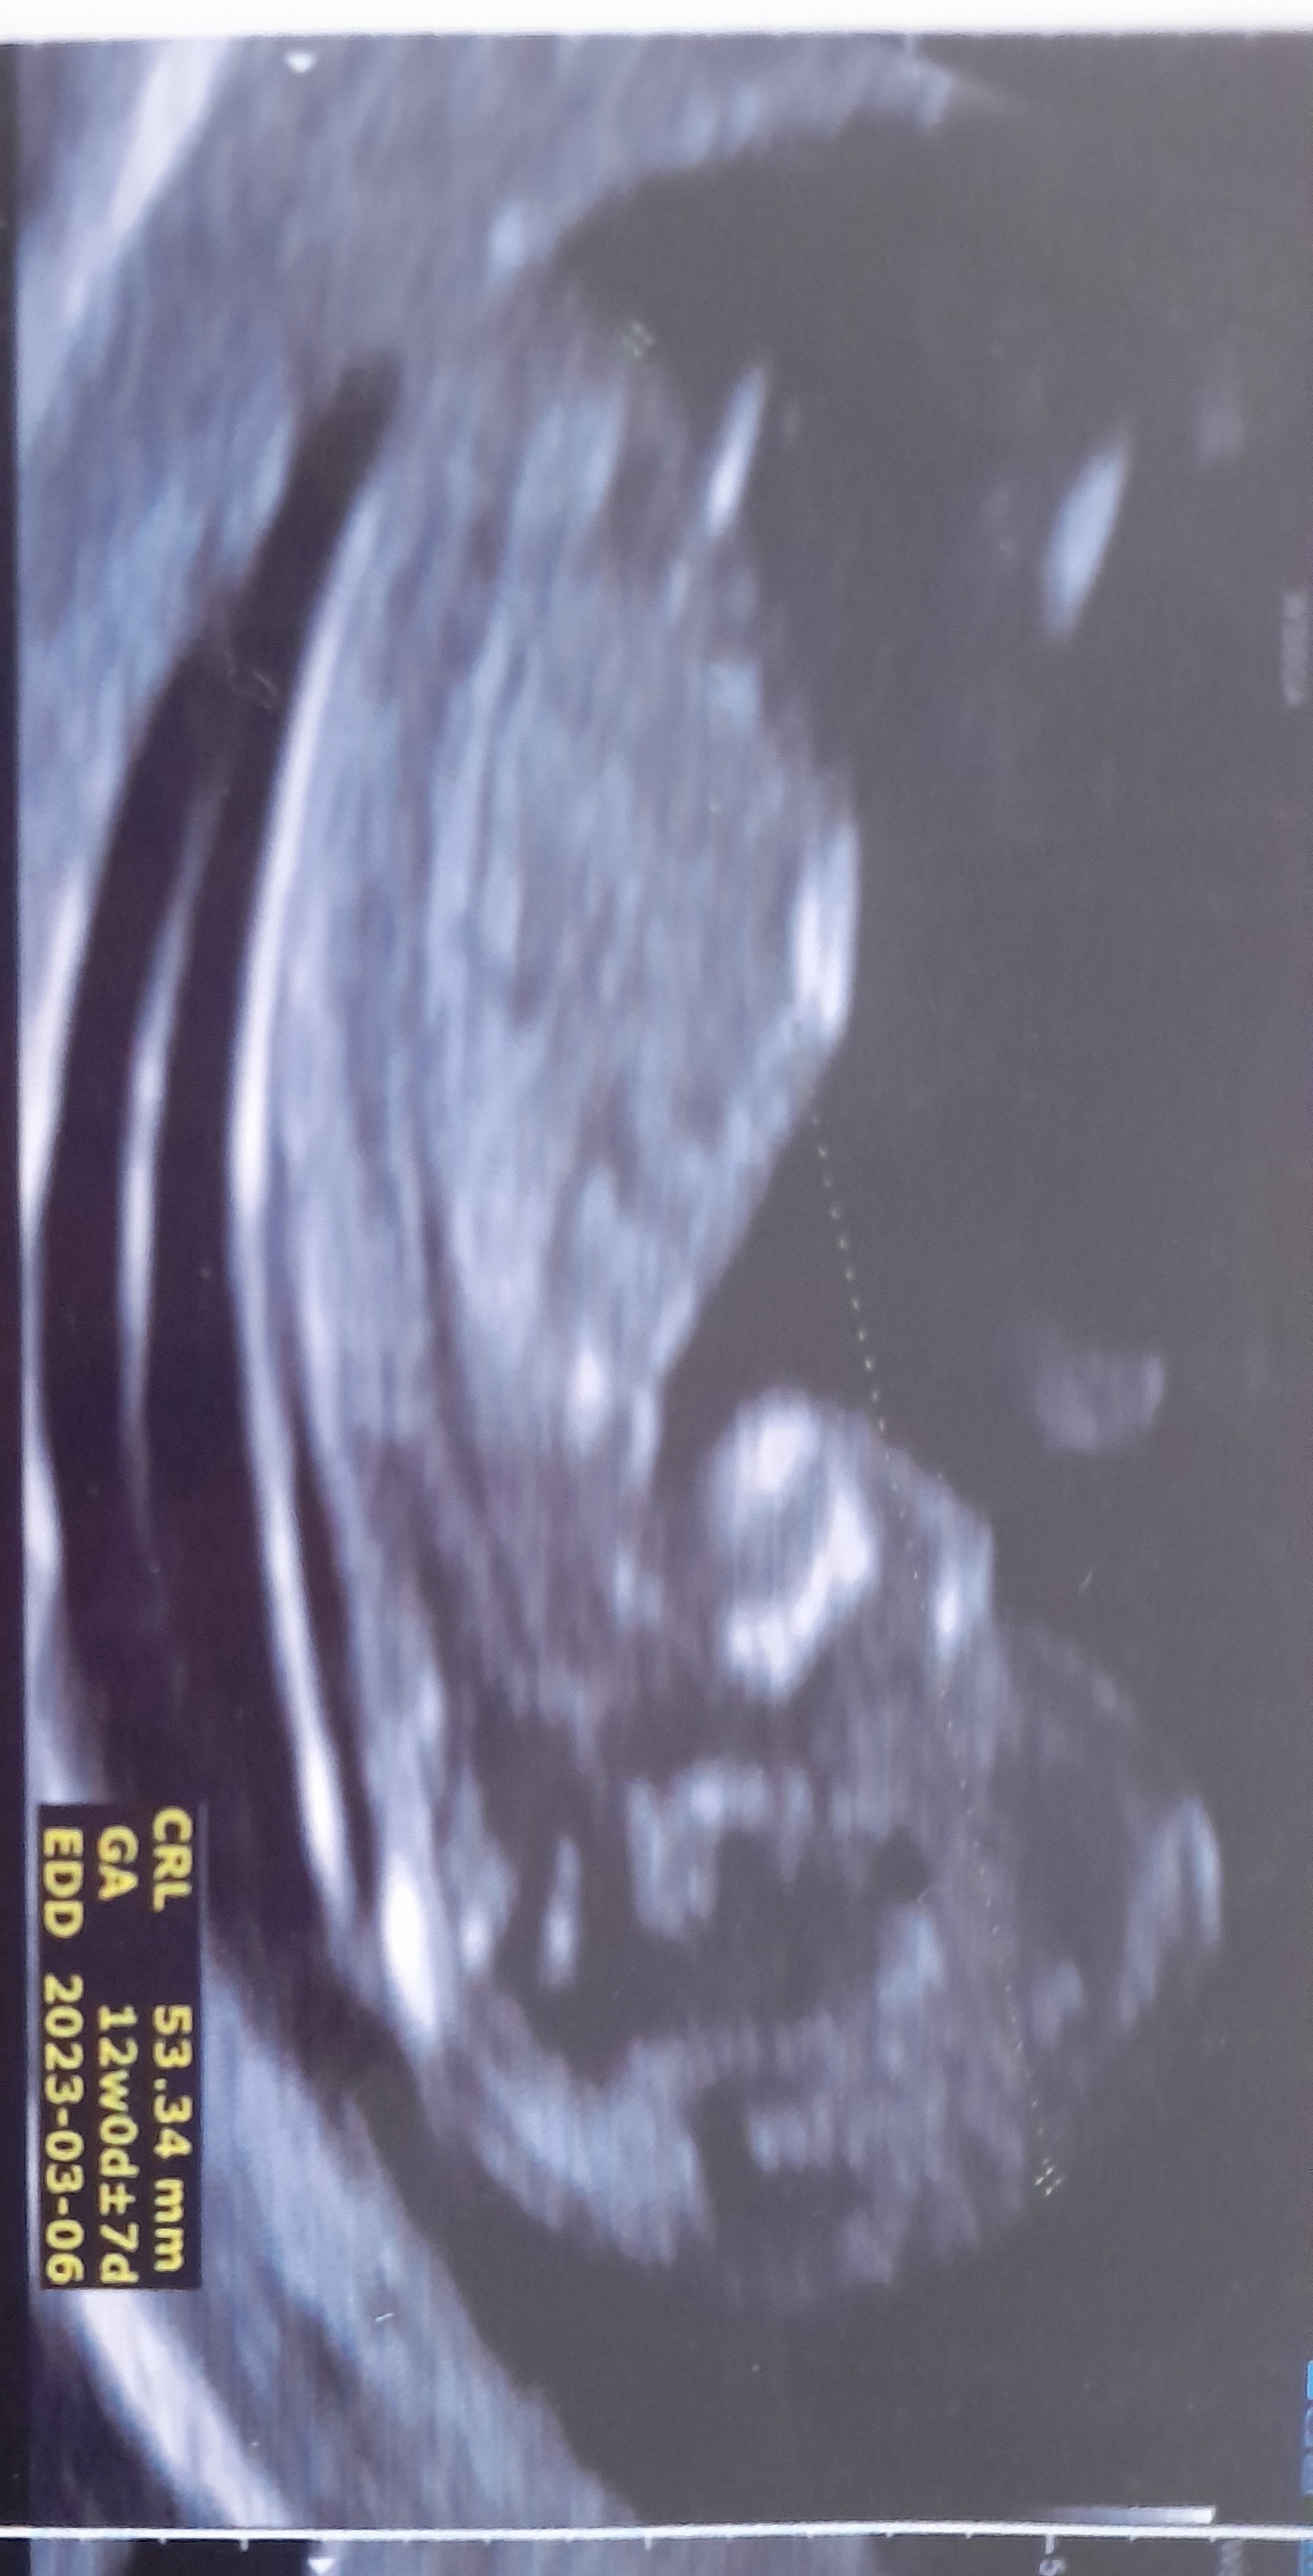

سونو ان تی +اونایی که بلدین بیایین ببینم نی نی ام چیه🥰

دختره عزیزم

از استخون جمجمه  با بچه من فرق داره. البته فقط یه حدسه

فک کنم یه گل دختره 😍 منم هفته پیش رفتم دکتر گفت ۸۰ درصد دختره عکسشو میزارم خودت مقایسه کن گلم  ...

منم از زاویه و جمجمه حدس دختر میزنم دکتر احتمال نداد؟